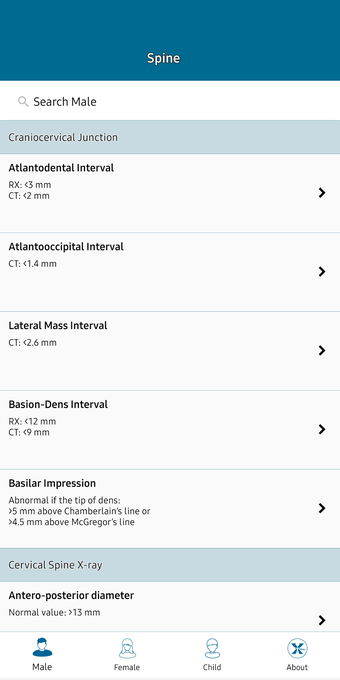

This helpful app is intended for all those who practice medical imaging and for the radiologists who use the application in their work. It is an atlas of the main measurements in radiology and their normal values, divided into six subspecialties: osteoarticular, cervical region, thorax, cardiovascular, abdomen, and pelvis.

The lessons are organized in a way that allows for easy and fast access to the information. In addition, the application has a section with a summary of the main points of the sub-specialties, which can help the user quickly grasp the meaning of the measurements and the importance of each of them.